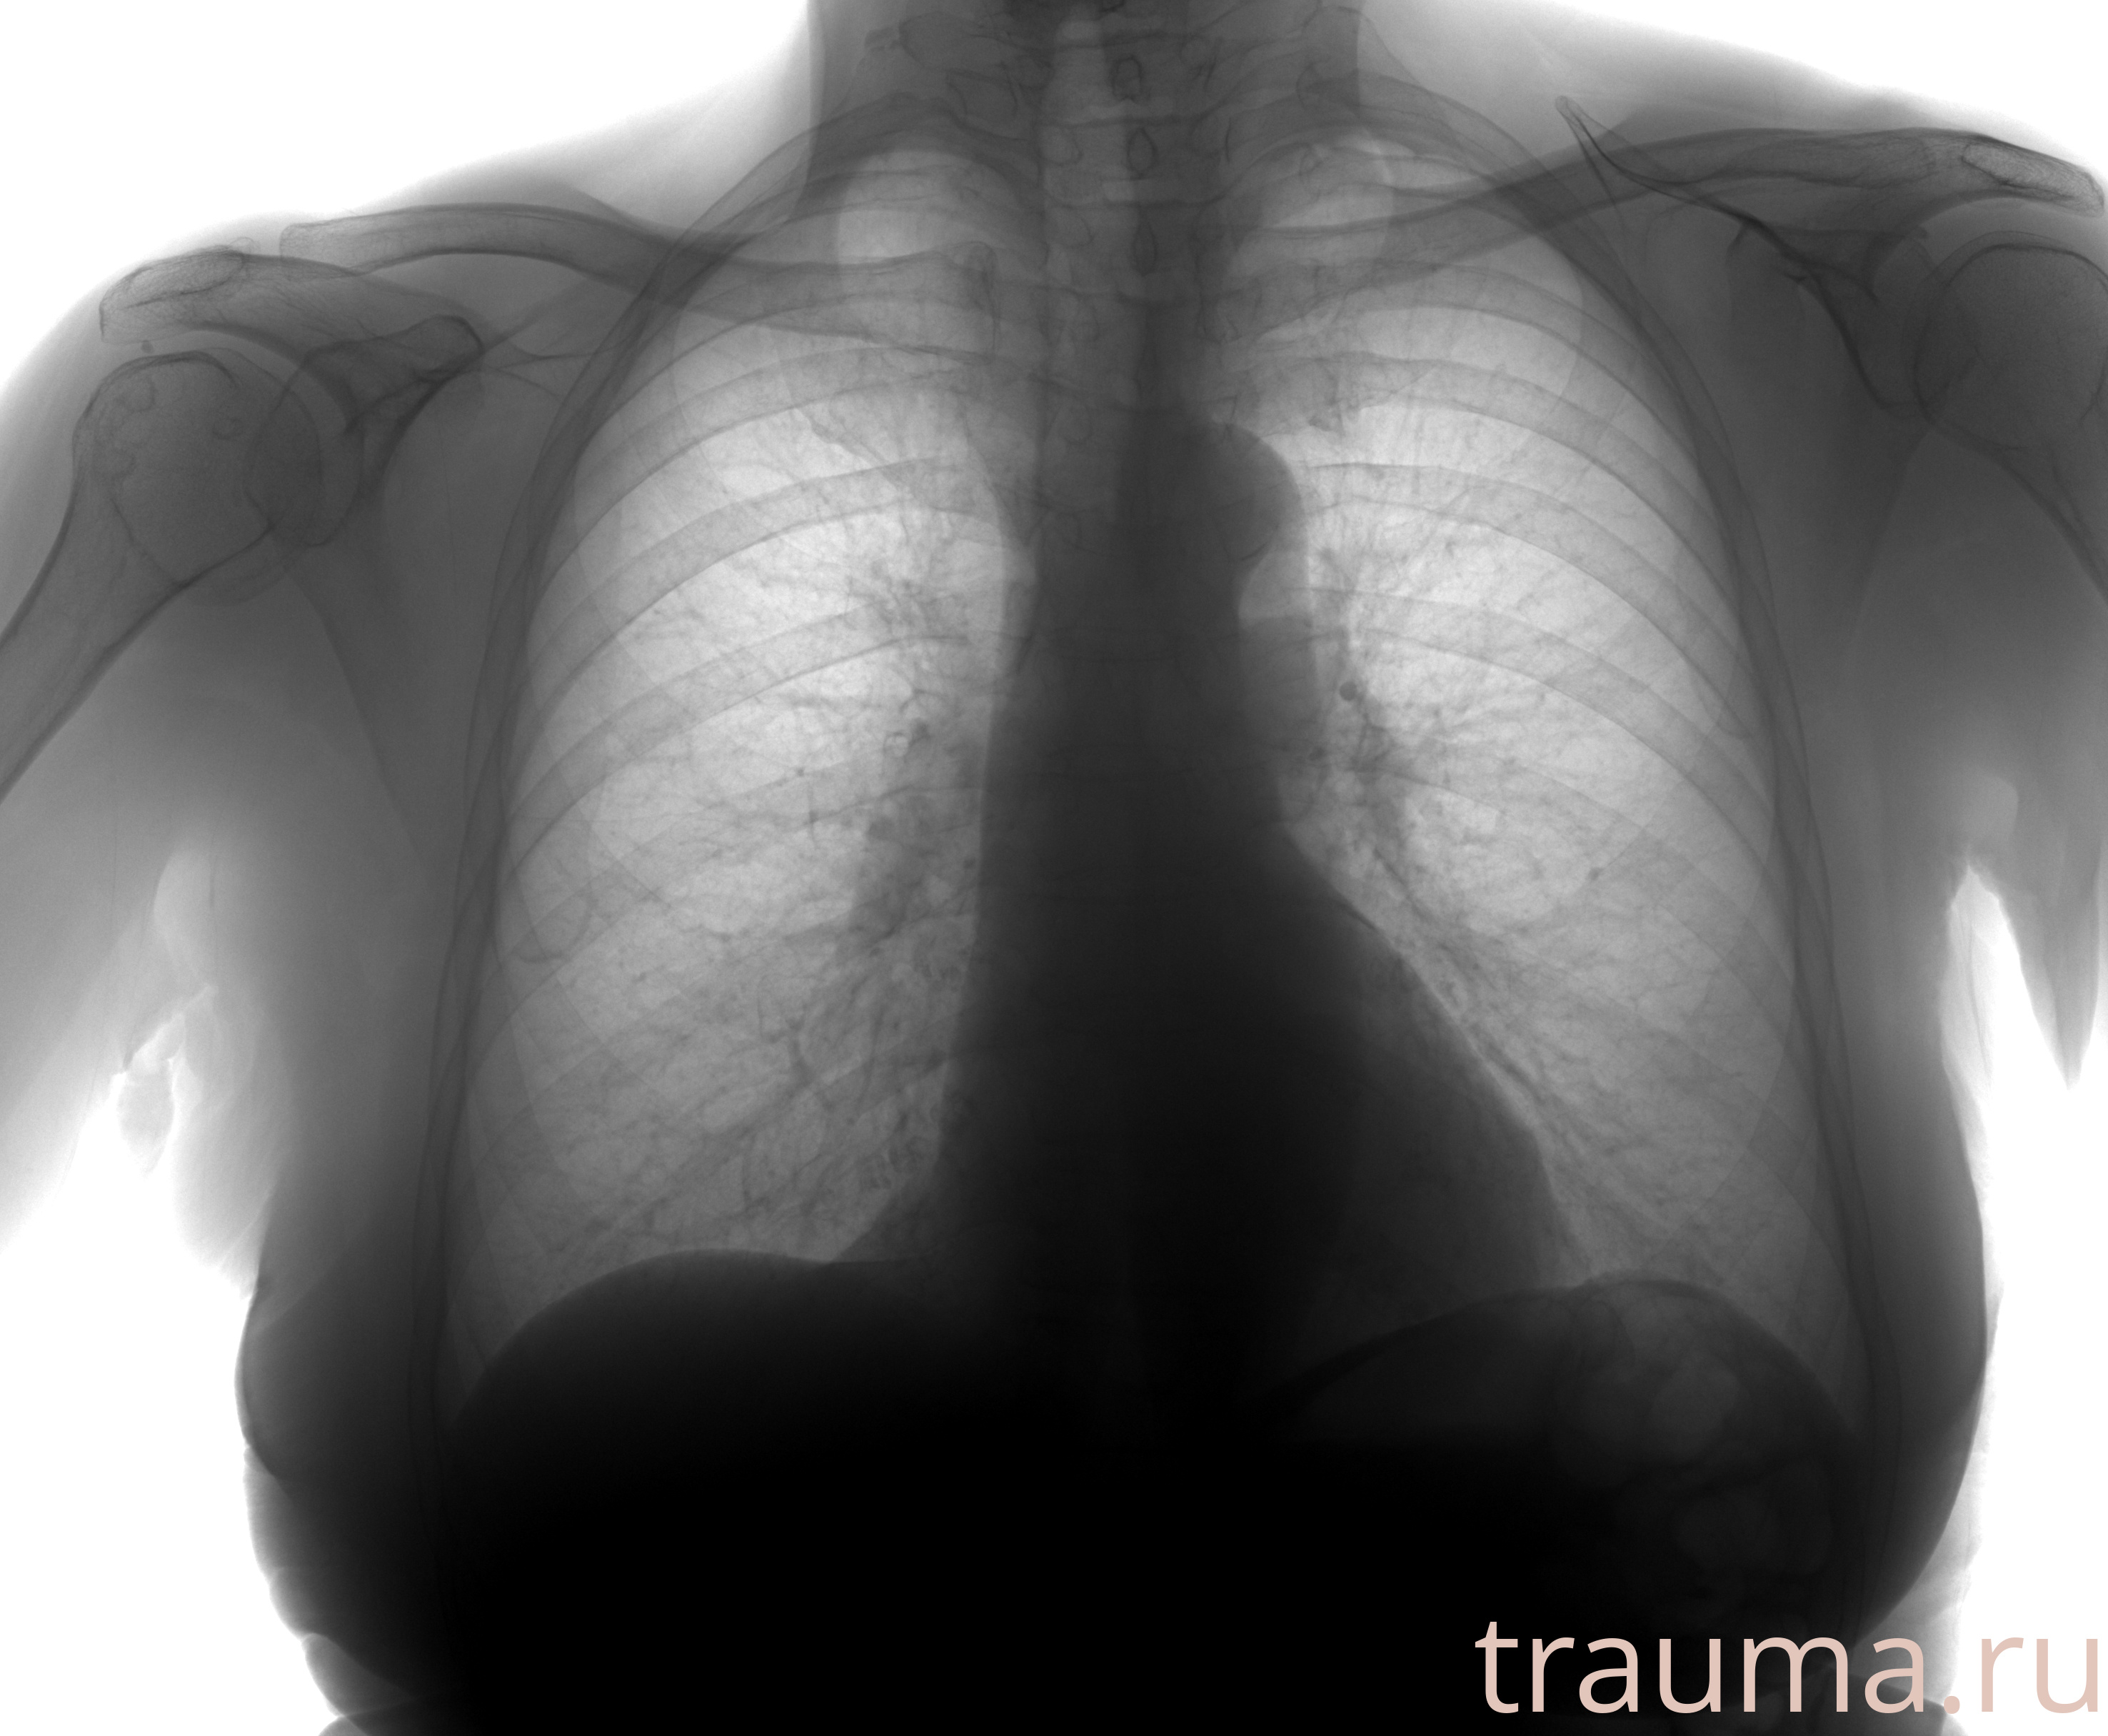

Рентген на дому: по вашему адресу приезжает врач-рентгенолог, травматолог-ортопед с мобильным рентгеновским аппаратом, проводит диагностику травмы или заболевания, делает необходимые рентгенограммы, дает рекомендации по дальнейшему лечению. Получить качественные снимки в домашних условиях возможно благодаря уникальной методике, разработанной МосРентген Центром для института  Склифосовского

при переломе шейки бедра и пневмонии от компании МосРентген Центр - партнера Института имени Склифосовского